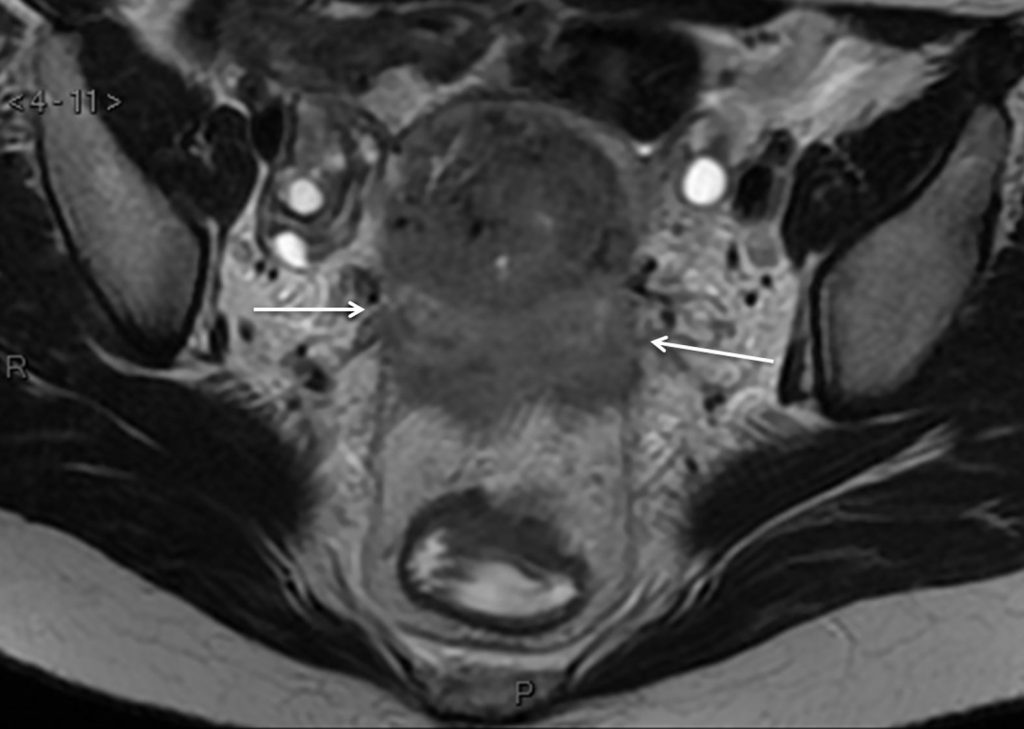

Le bilan d’extension lésionnel doit être évalué dans les trois plans de l’espace. L’IRM (figure 21.2), en accord avec la classification FIGO ou TNM, doit préciser impérativement :

- la taille de la tumeur (grand axe tumoral inférieur ou supérieur à 4 cm) ;

- et la présence ou non d’une extension paramétriale et lymphatique pelvienne et lombo-aortique.

Fig. 21.2 Coupe IRM en incidence axiale pondérée en T2 retrouvant une extension tumorale paramétriale bilatérale (flèches).

Source : CERF, CNEBMN, 2022.

Ces éléments conditionnent le type de prise en charge thérapeutique, chirurgicale d’emblée ou non.